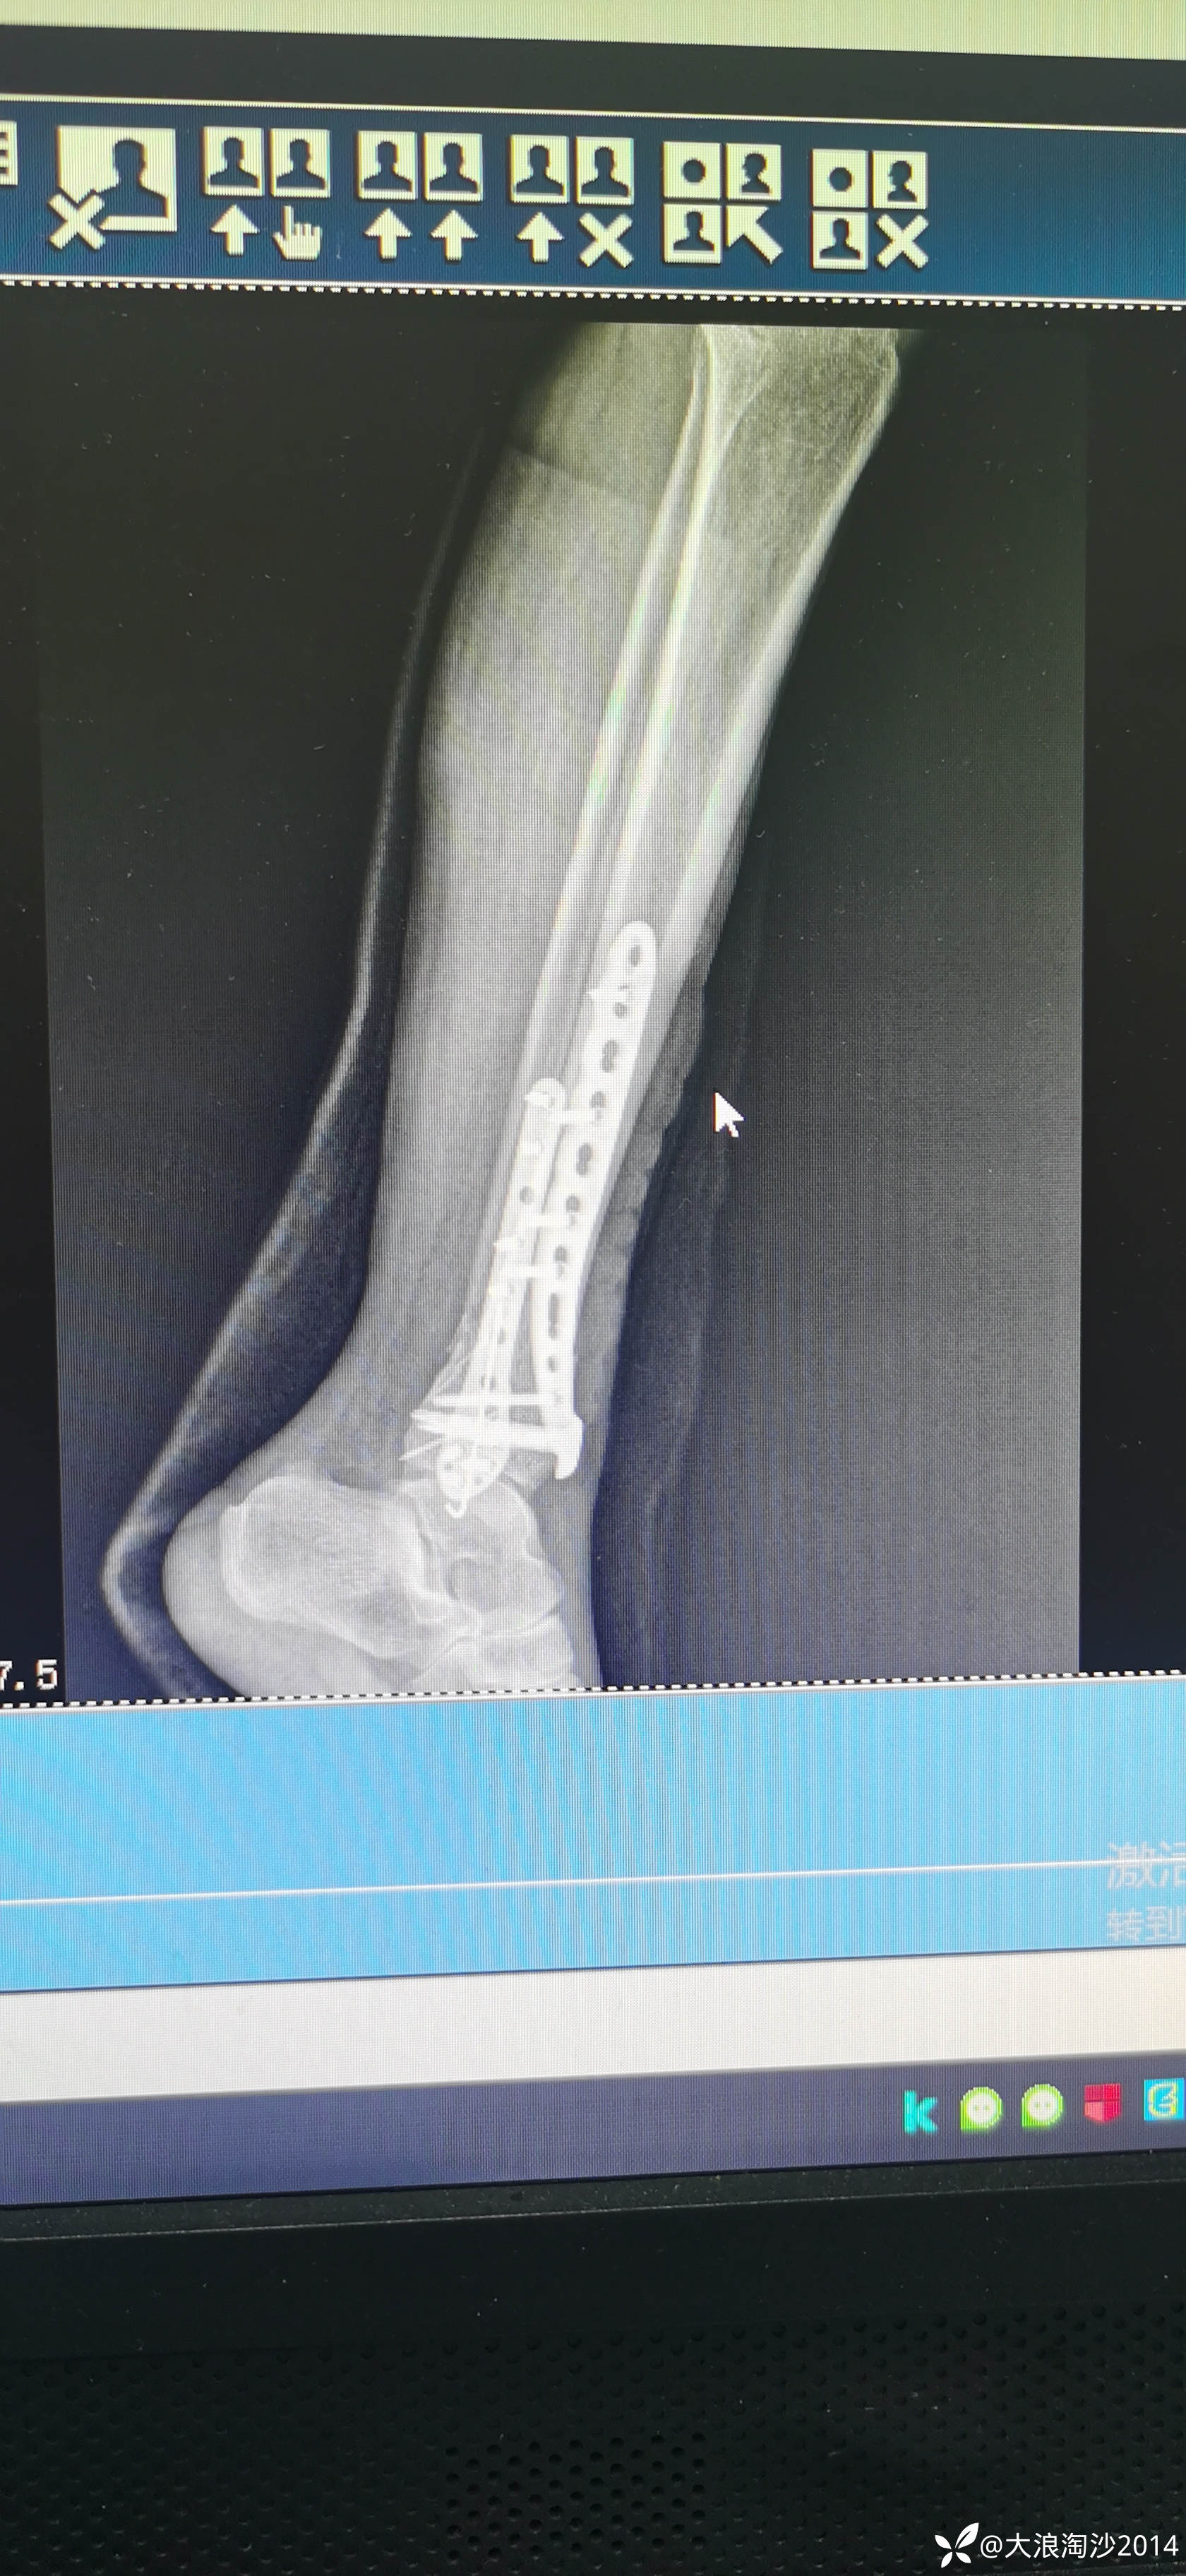

一65岁女性患者,偏瘦,体重75斤,车祸外伤致左胫腓骨远端骨折,入院后消肿后,病人可以用皮包骨头形容,考虑胫骨远折端不适合用内侧插板(mippo技术),病人太瘦,如取两个切口分别处理胫腓骨,切口容易出现问题,因此采用前外侧一个切口处理胫腓骨远端骨折(片子顺序上传有点乱)